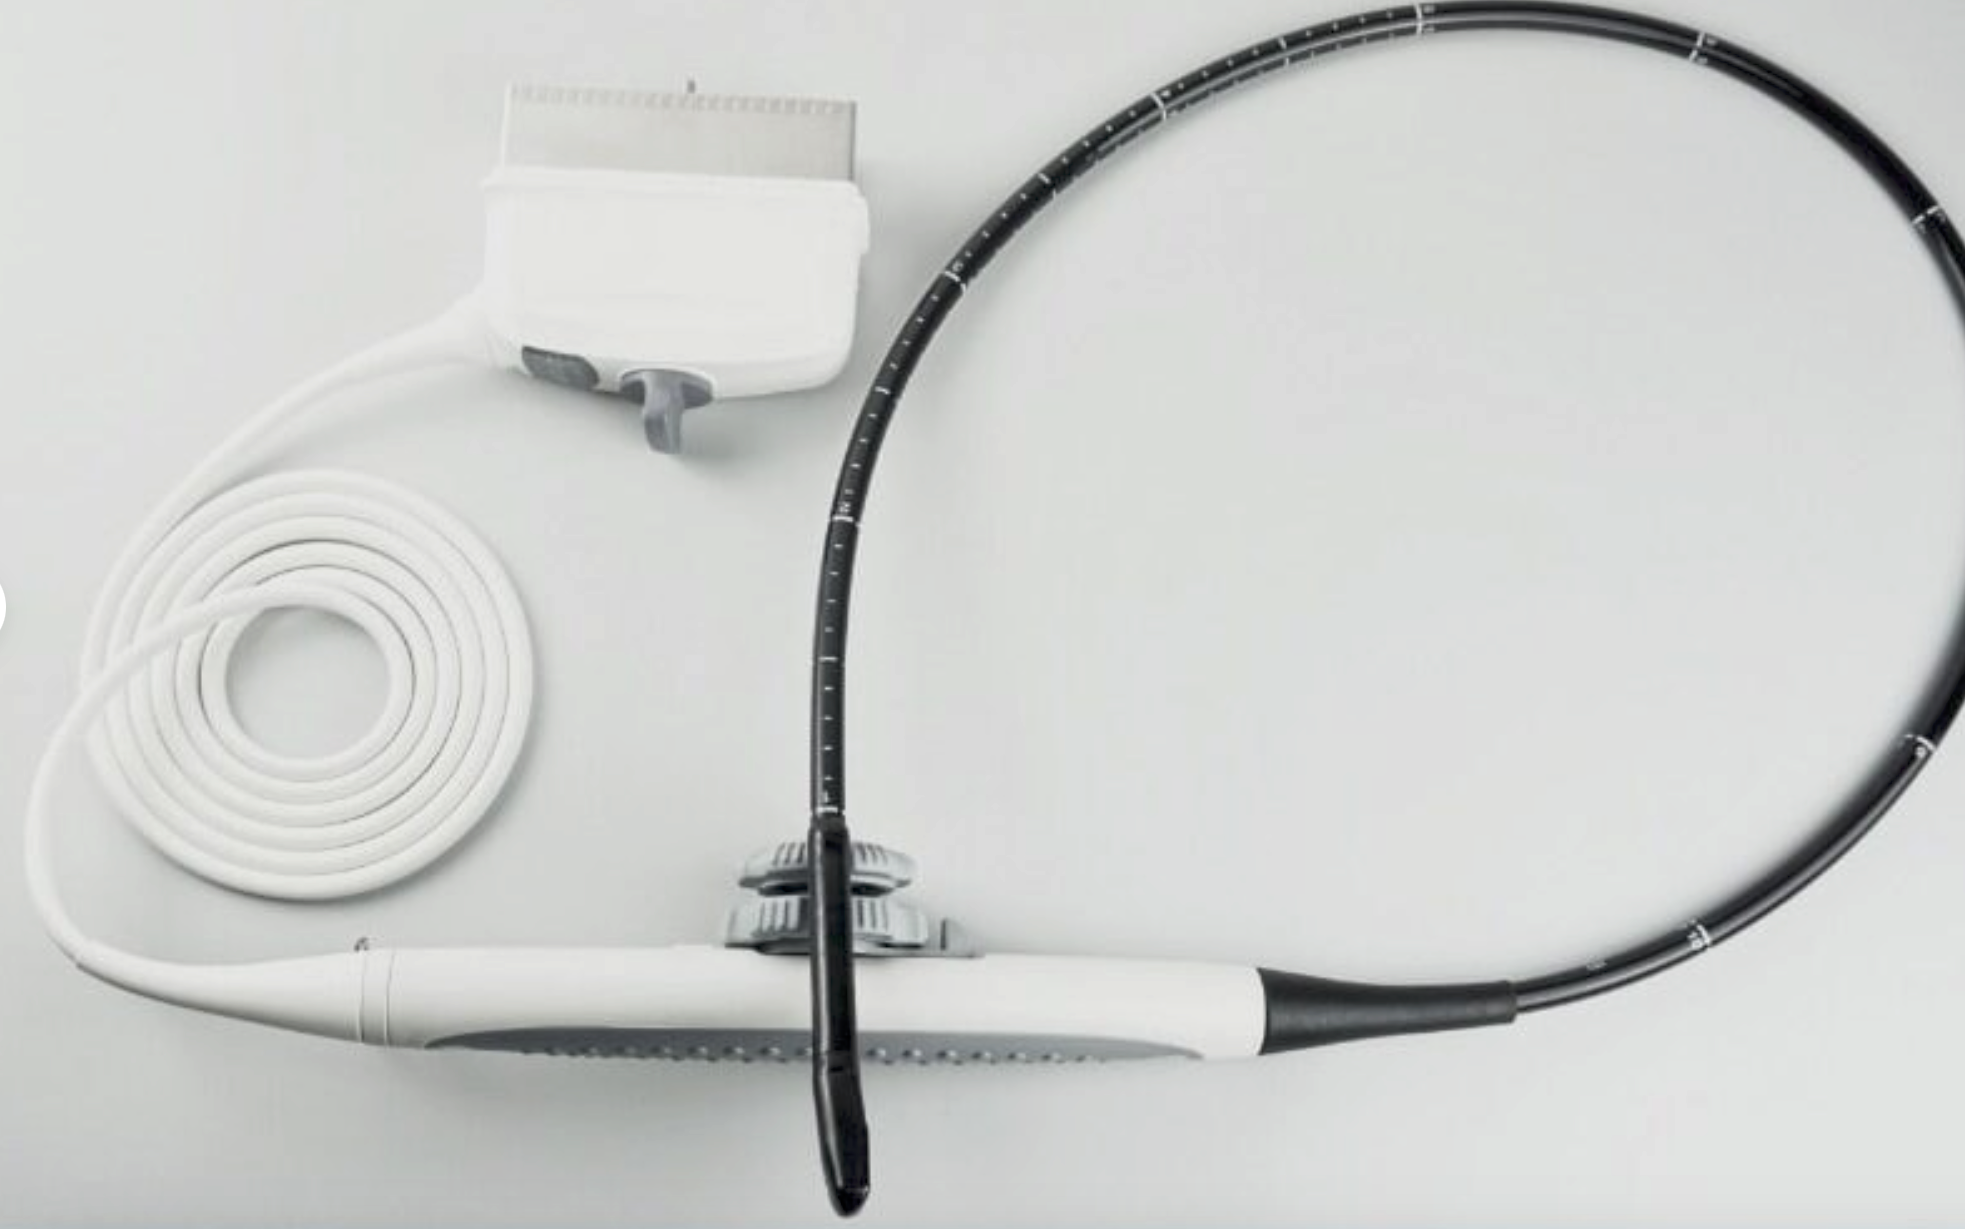

Seller Notes:âTested using a Logiq P5 Ultrasound unit. Plugs into ultrasound and produces image. Image has dead zones and white bars inconsistent with other functional transducers (pictured). Show signs of use. Includes everything shown. Sold AS IS.â